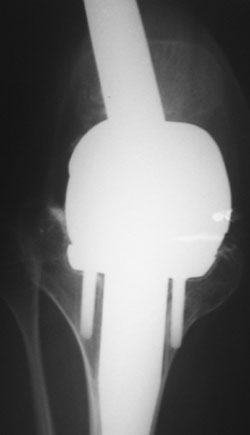

Уважаемые коллеги!У нас наблюдается пациент, 22 лет.В 1993 году -субтотальная резекция бедренной кости (остеогенная саркома -по выписке), установленэндопротез коленного сустава.

A male 22 years old sustaned subtotal resection of the femur because of osteosarcoma. A total knee

was implanted.

"subtotal resection of the femur for osteosarcoma" How much femur was removed or left? It's hard to tell from the radiographs.

Is the intramedullary device seen on the AP radiograph of the hip a component of the total knee replacement or something else?

TAC> Is the intramedullary device seen on the AP radiograph of the hip a component

TAC> of the total knee replacement or something else?

Yes, it is a long stem onco implant.